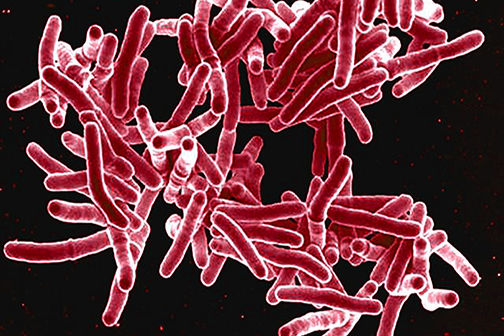

LSU Health New Orleans Discovers Major Contributor to Alzheimer’s Disease

Research led by Drs. Yuhai Zhao and Walter J Lukiw at the LSU Health New Orleans Neuroscience Center and the Departments of Cell Biology and Anatomy, Neurology and Ophthalmology, reports for the first time a pathway that begins in the gut and ends with a potent pro-inflammatory toxin in brain cells contributing to the development of Alzheimer’s disease (AD). They also report a simple way to prevent it. More